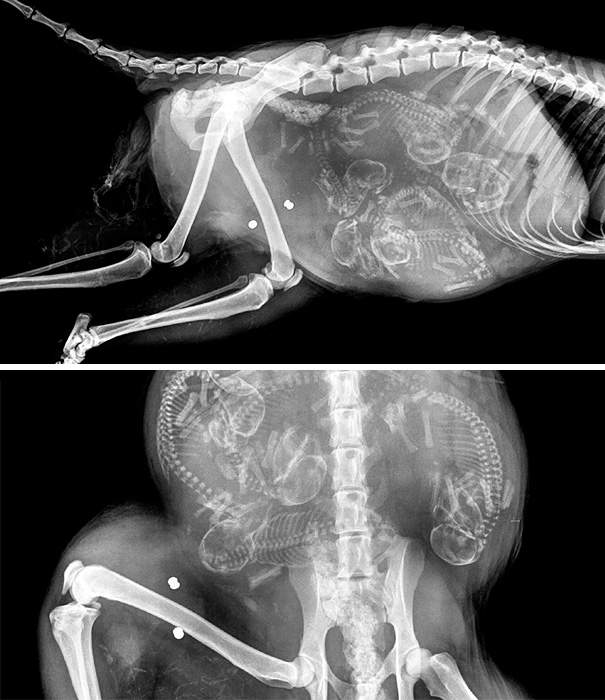

▼懷孕的天竺鼠

圖片來自:boredpanda